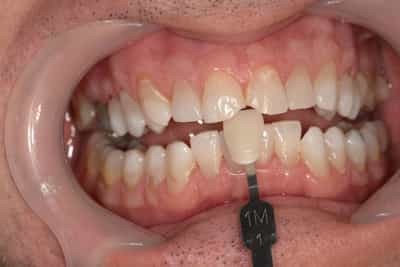

Cas numero 2 :

Situation Initiale

Etude du cas et proposition